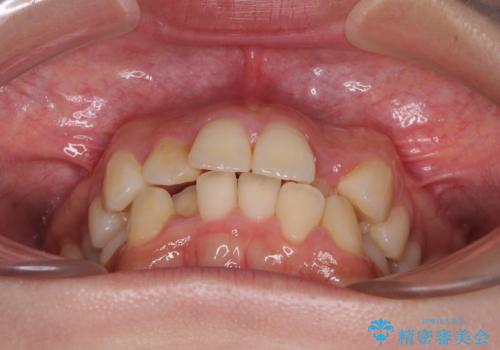

- 上下のデコボコと前歯のクロスバイトを改善したいとのことで来院された患者様です。

極力短期間で治療したいとのことで、ワイヤー装置による矯正治療を行うこととしました。

マウスピースによる矯正治療も提案しましたが、ご自身でのマウスピースの管理の面倒くささと、なるべく早く治療を終えたいとのことで、ワイヤー矯正を選択されました。